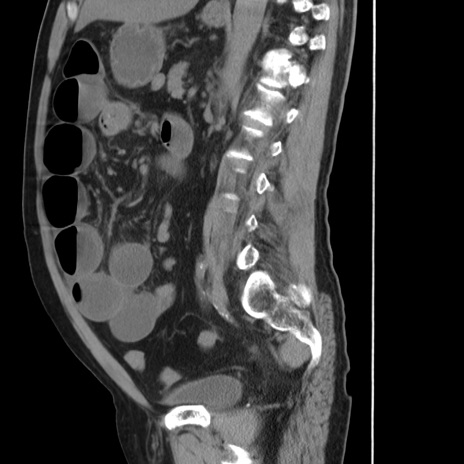

症例20(矢状断像)

【症例】 60歳代男性

【主訴】 腹部膨満、嘔吐

【現病歴】5日前頃より倦怠感を認め食事量減少し4日前の朝嘔吐、食事摂取困難となった。 3日前近医受診し点滴施行され整腸剤などを処方された。 当日他院を受診し、腹部膨満著明、炎症反応の上昇(CRP10.8、WBC11200)あり、紹介受診となる。

【身体所見】 意識JCS1 受け答えがはっきりしないBP 111/57mHg、 P 67bpm、、BT35.2°C、SpO2 97%(RA)、 腹部:膨隆、打診で鼓音あり、全体的に圧痛有り、腸蠕動音(-)、反跳痛ははっきりせず。

【データ】WBC 11400、CRP 14.20